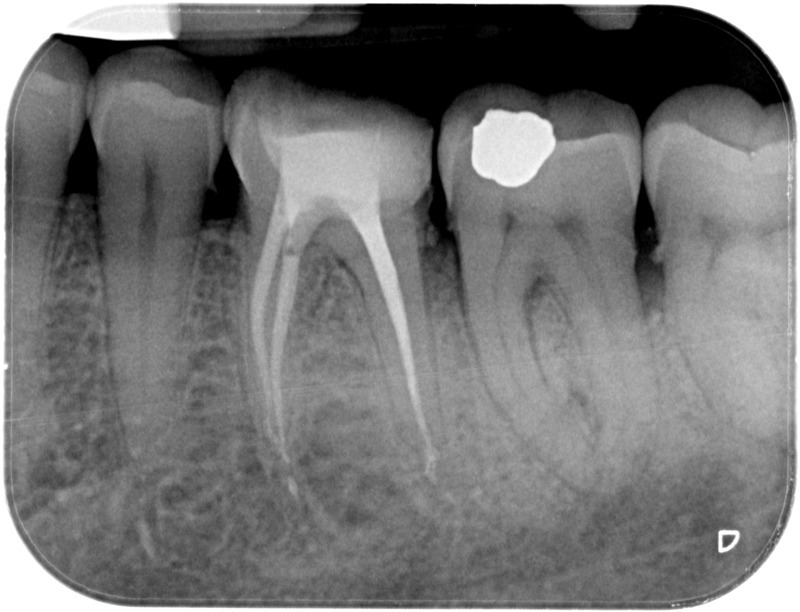

• Traitement endodontique : Sous anesthésie locale et à travers la protection d’un champ opératoire nous accédons à la pulpe de la dent à soigner, puis aux canaux de ses racines que nous devons désinfecter. Ce soin nécessite l’élimination complète de la source de contamination (souvent la carie) parfois sous une ancienne reconstitution ou une couronne qu’il faut alors retirer. Une fois le nettoyage et la mise en forme des canaux réalisés, nous les obturons de façon hermétique avec un ciment et un matériau thermoplastique appelé Gutta Percha. Ceci afin d’empêcher une nouvelle prolifération bactérienne et d’assurer le maintien de la dent dans ses structures de soutien (ligament parodontal et os alvéolaire). L’ouverture effectuée au centre de la dent sera d’abord refermée avec un pansement provisoire avant d’envisager ensemble la reconstitution d’usage : un composite, un inlay-onlay ou une couronne.

• Reprise de traitement endodontique : La manœuvre consiste à retourner à l’intérieur des racines d’une dent déjà traitée. Il arrive occasionnellement qu’une nouvelle inflammation se déclare suite à une reprise de carie ou une fracture de la dent, ou si le premier traitement endodontique est incomplet. Après s’être assuré que la dent lésée était conservable, il convient de désinfecter de nouveau le réseau canalaire parfois très complexe. La nouvelle obturation des canaux devra être protégée aussi rapidement que possible pour éviter une éventuelle contamination bactérienne.